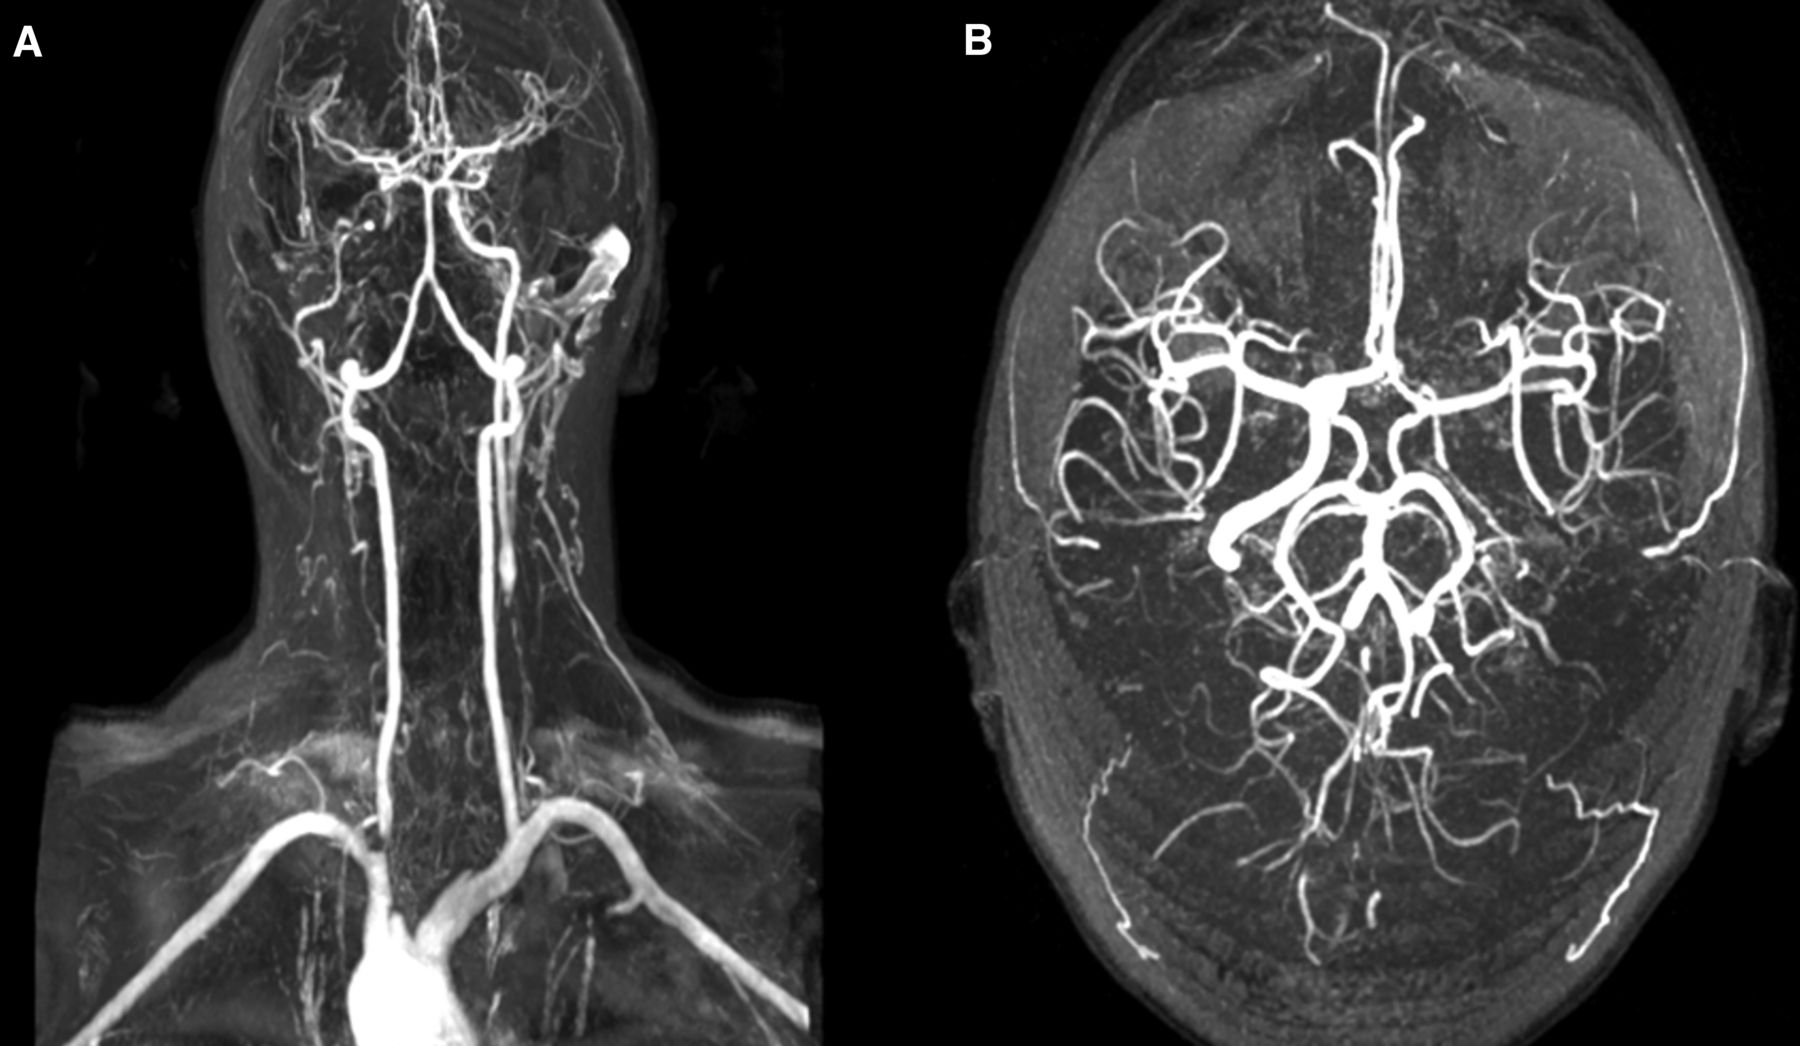

Kiểm tra hình ảnh như chụp cắt lớp vi tính (CT Scan), chụp cộng hưởng từ (MRI) thường là cần thiết.

Chẩn đoán được xác nhận bởi một sự kết hợp của các triệu chứng, kết quả xét nghiệm, tốc độ máu lắng ESR và Protein C-reactive CRP cao, bất thường tại mạch máu đặc trưng được tìm thấy trên kiểm tra hình ảnh.